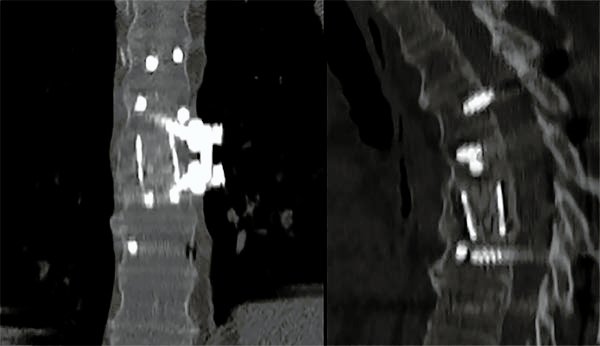

Figura 5:

Caso 8. Se realizó una estabilización percutánea T6-T10. El paciente retornó a UTI, para estabilizar su cuadro respiratorio y hemodinámico.

Figura 6:

Caso 8. A la semana de la primer cirugía el paciente se encontraba en condiciones y se realizó la corpectomía por via lateral MIS.

Figura 7:

Caso 8. Control postoperatorio alejado del paciente con un buen callo de fusión, sin pérdida de corrección.